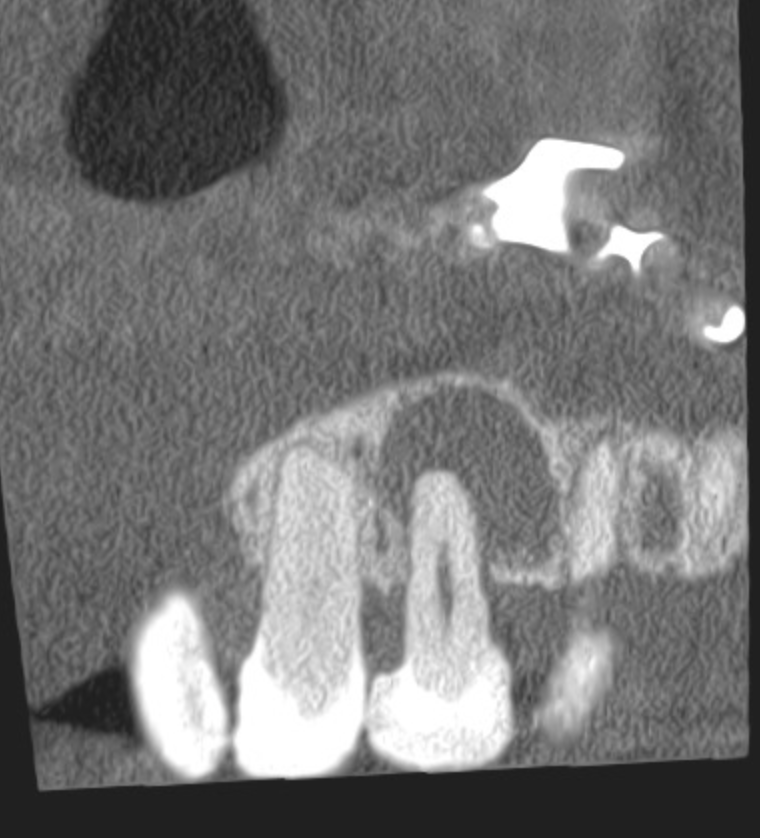

Vertical root fracture